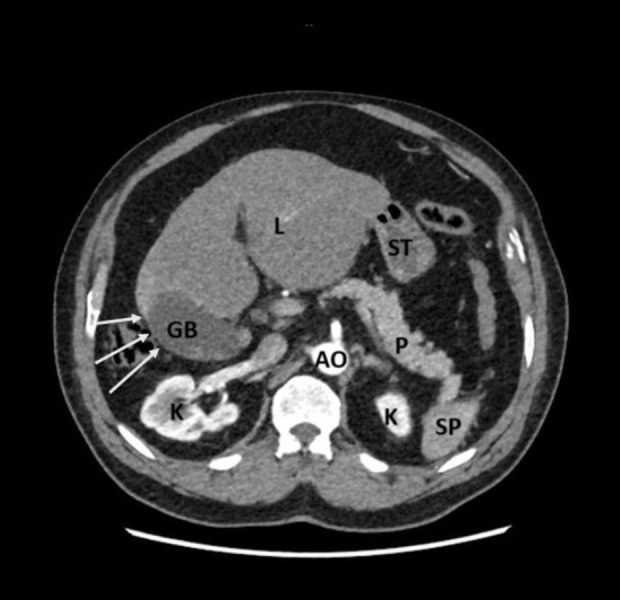

背景右肝叶发育不全是一种罕见的先天性异常,通常在影像学或外科手术中偶然发现。这种异常在手术中可能具有挑战性,导致术中并发症。右肝发育不全患者通常生活正常,无症状,但可合并肝硬化、门静脉高压症和胆结石。虽然先天性肝发育不全和胆囊炎之间的确切病理生理关系尚不清楚,但已经提出了一些促成因素。这些包括肝细胞核因子1B (HNF1B)转录的突变,胆囊功能受损以及由于位置不当导致的胆囊缺血。病例报告:一名70岁男性表现为坏疽性胆囊炎并并发右肝叶发育不全;以前没有记录的组合。患者最初无症状,表现为剧烈的胃脘痛,经腹部超声诊断为急性胆囊炎。然而,计算机断层扫描(CT)成像显示右肝叶严重发育不全,伴有左肝叶代偿性肥大,胆囊结石。尽管实验室结果正常,但我们认为这种异常延迟了诊断,直到发展为胆囊炎作为并发症。患者接受了成功的腹腔镜胆囊切除术,没有转到开放手术。结论:本病例强调了在计划手术时识别解剖变异的重要性。意识到右肝叶发育不全有助于及时诊断和适当处理,最终减少手术风险和并发症。此外,我们建议在急性胆囊炎症状不明确或不典型的情况下,以及腹部超声(US)显示胆囊位置异常时,进行CT检查。然而,我们建议在手术中确定解剖结构,以避免并发症。

BACKGROUND Hypoplasia of the right hepatic lobe is a rare congenital anomaly often discovered incidentally during imaging or surgery. This anomaly can be challenging during surgery, leading to intraoperative complications. Patient with right hepatic hypoplasia usually live normally without symptoms, but it can be associated with liver cirrhosis, portal hypertension, and gallstones. While the exact pathophysiological relationship between congenital hepatic hypoplasia and cholecystitis remains unclear, a few contributing factors have been proposed. These include mutations in the hepatocyte nuclear factor 1B (HNF1B) transcription, impaired gallbladder function, and gallbladder ischemia due to malposition. CASE REPORT A 70-year-old man presented with gangrenous cholecystitis and concurrent hypoplasia of the right hepatic lobe; a combination not previously documented. The patient, initially asymptomatic, presented with sharp epigastric pain and was diagnosed with acute cholecystitis through abdominal ultrasound. However, computed tomography (CT) imaging showed severe hypoplasia of the right liver lobe with associated compensatory hypertrophy of the left lobe in addition to stones in the gallbladder. Despite normal laboratory results, we think that the anomaly delayed the diagnosis until the development of cholecystitis as a complication. The patient underwent a successful laparoscopic cholecystectomy without converting to open surgery. CONCLUSIONS This case underscores the importance of recognizing anatomical variations when planning surgery. Awareness of right hepatic lobe hypoplasia can aid in timely diagnosis and appropriate management, ultimately reducing surgical risks and complications. Furthermore, we recommend performing CT in case of vague or atypical symptoms of acute cholecystitis, as well as when the gallbladder shows malposition on abdominal ultrasound (US). However, we recommend identifying the anatomical structure during the surgery to avoid complications.